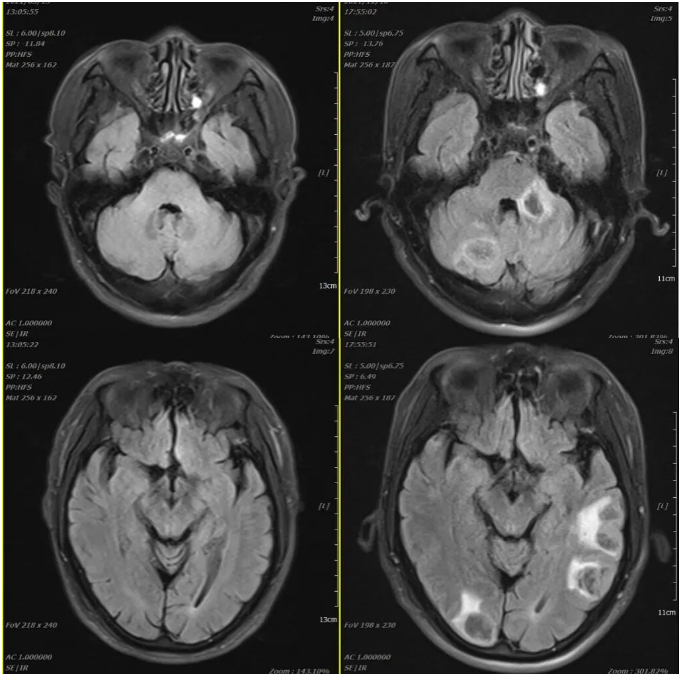

2021-07-06 2021-12-11

2021-03-05 2021-12-10

2021年12月11日疗效评价:PD(两肺及胸膜结节明显增多、增大;纵隔前间隙、纵隔内及两肺门转移淋巴结(现约4.7×3.5cm)较前增多、增大,上腔静脉、左头臂静脉受累狭窄;双侧小脑半球、大脑半球转移(约2.1×1.7cm)新发。

2021-12-11 2022-03-23

2周期治疗后 疗效评估:PR(部分缓解)